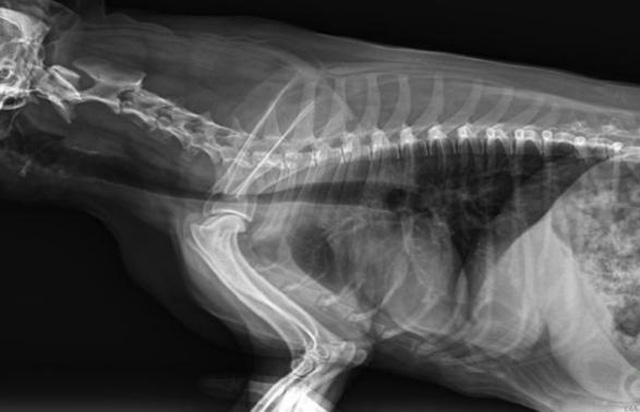

精準(zhǔn)的診斷為小動(dòng)物保駕護(hù)航寵物DR的操作流程是什么呢?

從臨床角度出發(fā),大力發(fā)展動(dòng)態(tài)DR,以精準(zhǔn)的診斷為小動(dòng)物保駕護(hù)航。寵物DR升級(jí)使用雙焦點(diǎn)球管,大尺寸平板探測(cè)器,超高頻逆變高壓發(fā)生器。醫(yī)用纖維板臺(tái)面,防止寵物劃傷。寵物DR整機(jī)小巧實(shí)用,骨略結(jié)構(gòu)和器官位置,分類詳細(xì),運(yùn)算更快,讓拍攝條件更科學(xué),有助于提高診斷的準(zhǔn)確性和效率。安裝移動(dòng)非常方便。低輸入電流設(shè)計(jì),220伏常規(guī)電壓。多品種動(dòng)物程序設(shè)定,滿足各個(gè)臨床需求。成像效果顯著,寵物不能言語表達(dá),導(dǎo)致誤診率居高不下。寵物診療均以經(jīng)驗(yàn)診斷為主的方式,確保最小化輻射降低對(duì)醫(yī)生及動(dòng)物的影響。以滿足精細(xì)化的寵物醫(yī)療需求,成為診斷寵物內(nèi)外科疾病的必備工具。使醫(yī)院更有競(jìng)爭(zhēng)力,為醫(yī)院創(chuàng)收增光添彩。

寵物DR的操作流程是什么呢?第一步首先插上整機(jī)電源,然后按下主機(jī)電源。打開高壓發(fā)生器的電源,工作站主機(jī)電源。等待主機(jī)軟件的自動(dòng)啟動(dòng)。通過軟件登記檢查的寵物信息,選擇寵物檢查拍攝部位。調(diào)節(jié)限速器拍攝區(qū)域。關(guān)閉鉛房門,點(diǎn)擊開始拍攝按鈕。拍攝完成調(diào)整圖像并且輸出。